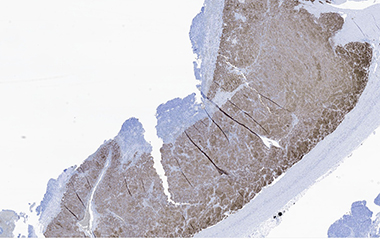

Synaptophysin and chromogranin were positive in pheochromocytoma areas. S100 and neurofilament were focally positive in spindle cell areas and sustentacular cells. Vimentin was positive in spindle cell areas. H3K27me3 showed focal areas with loss of expression. Inhibin was positive in focal areas, consistent with entrapped cortical cells.

E. Pheochromocytoma with positive synaptophysin stain